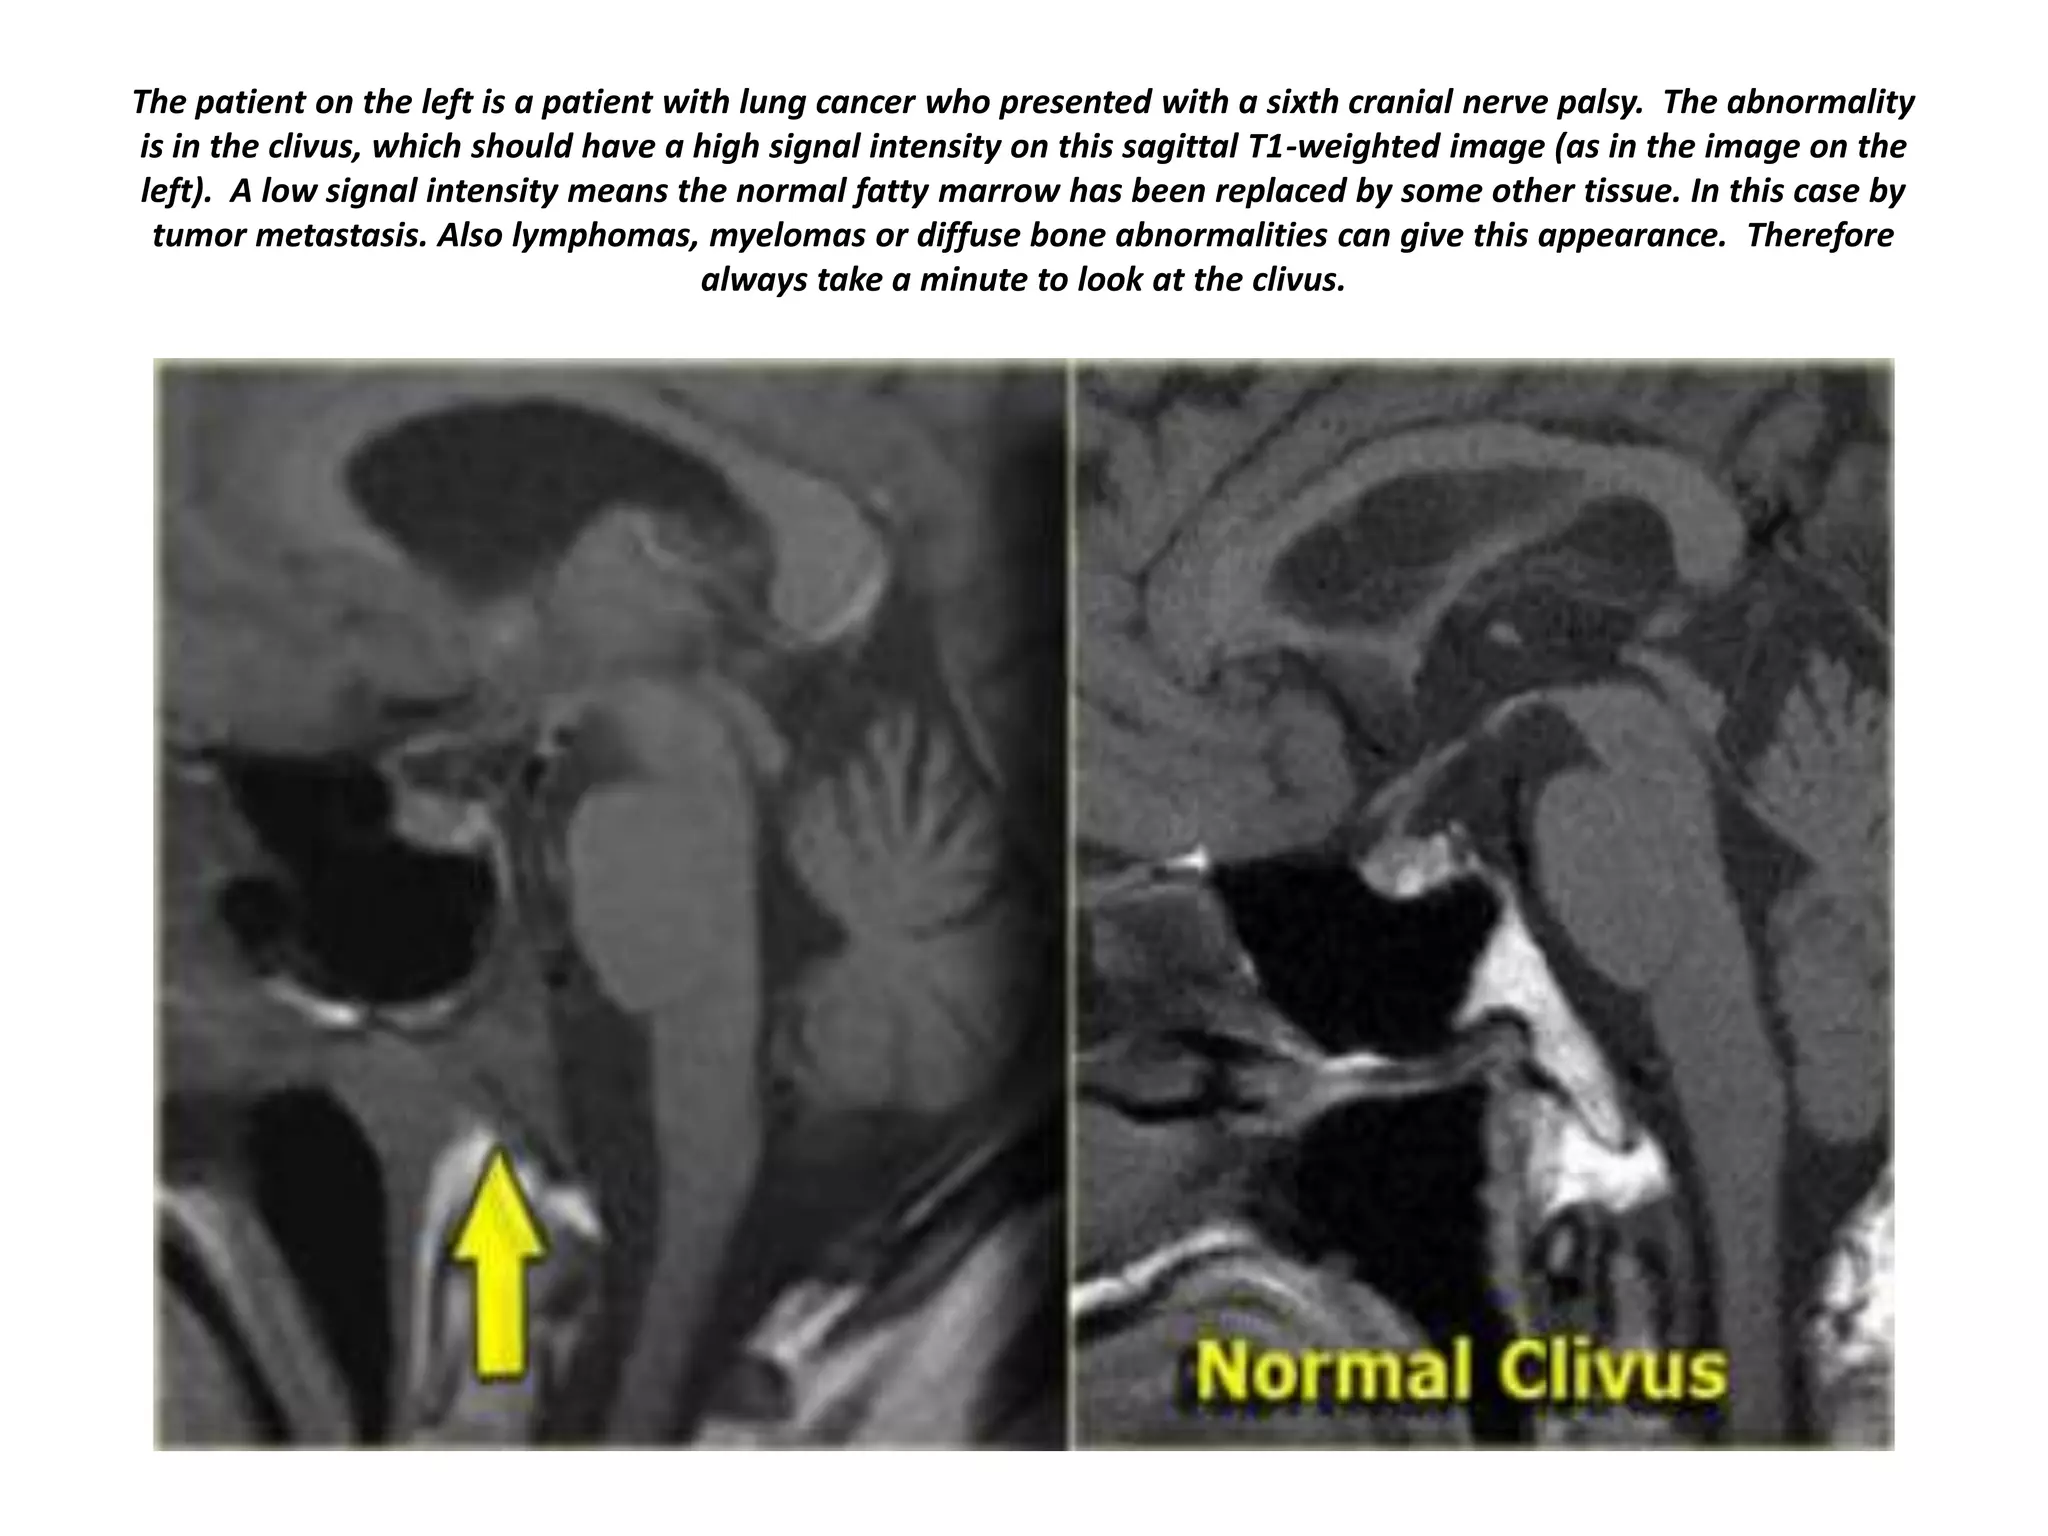

The patient on the left is a patient with lung cancer who presented with a sixth cranial nerve palsy. The abnormality

is in the clivus, which should have a high signal intensity on this sagittal T1-weighted image (as in the image on the

left). A low signal intensity means the normal fatty marrow has been replaced by some other tissue. In this case by

tumor metastasis. Also lymphomas, myelomas or diffuse bone abnormalities can give this appearance. Therefore

always take a minute to look at the clivus.